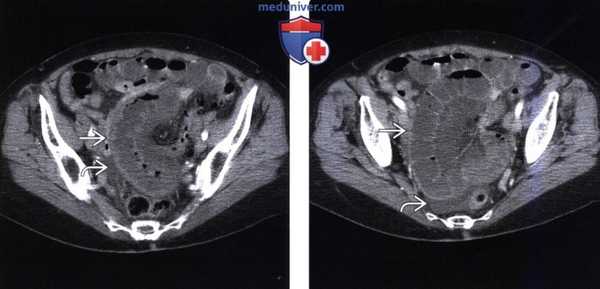

(Слева) На аксиальной КТ с контрастным усилением у мужчины 24 лет с жалобами на боль определяется тромб в просвете верхней брыжеечной и воротной вены. Тонкая кишка в значительной степени расширена и заполнена жидкостью. Стенка кишки утолщена, также определяется асцит: эти изменения позволяют заподозрить ишемию всех слоев стенки (трансмуральную).

(Справа) Обратите внимание на переполненные кровью брыжеечные вены и отек брыжейки у этого же пациента, что типично для венозного тромбоза и обусловленной им ишемии кишечника. Было обнаружено, что пациент находится в состоянии гиперкоагуляции, он дал ответ на анти коагуляционную терапию.

(Слева) На аксиальной КТ с контрастным усилением определяется утолщение стенки тощей кишки в правой половине живота вследствие врожденного нарушения поворота. Обратите внимание на измененное положение верхних брыжеечных сосудов и ограниченный асцит . При операции были обнаружены ишемические изменения кишечника в сочетании со спайками.

(Справа) На аксиальной КТ с контрастированием определяется асцит, а также инфильтрация брыжейки около сегментов тонкой кишки с утолщенной стенкой и расширением просвета, что позволяет сделать вывод об обструкции по типу закрытой петли и ишемии. Проксимальные отделы тонкой кишки и ободочная кишка имеют нормальный поперечный размер. (Слева) На рентгенограмме в косой проекции, полученной во время рентгеноскопического исследования пассажа бариевой взвеси по тонкой кишке, определяется сужение просвета и отсутствие нормальной складчатости, характерной для тонкой кишки, в подвздошной кишке, наряду с дилатацией более проксимальных отделов.